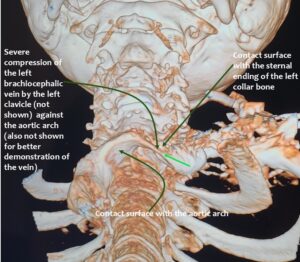

In addition, the patient had compression of the left brachiocephalic vein.

Consequently, blood had difficulty leaving the skull, resulting in continuously increased pressure and severe headaches, as well as other neurological dysfunction. The left side was more affected due to the double compression. This was clearly demonstrated by four-dimensional volume flow measurements in both jugular veins.